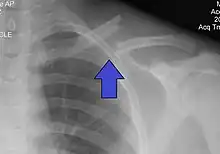

| X-ray of a left clavicle fracture | |

The basic method to check for a clavicle fracture is by an X-ray of the clavicle to determine the fracture type and extent of injury. In former times, X-rays were taken of both clavicle bones for comparison purposes. Due to the curved shape in a tilted plane X-rays are typically oriented with ~15° upwards facing tilt from the front. In more severe cases, a computerized tomography (CT) or magnetic resonance imaging (MRI) scan is taken. However, the standard method of diagnosis through ultrasound imaging performed in the emergency room may be equally accurate in children.[5]